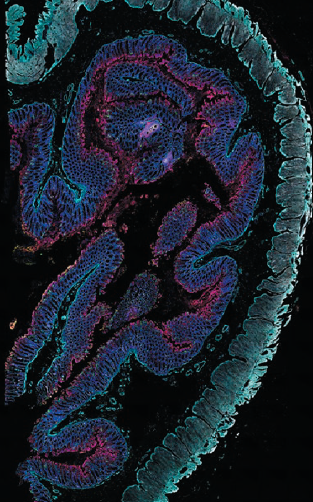

図4. より多くのターゲット検出による、組織微小環境に関する詳細情報の取得と、組織内生物学的システムの複雑性の可視化 EVOS S1000 Spatial

Imaging Systemを用い、9 plexで染色した正常結腸組織(左)および結腸腺がん組織(右)の画像です。マルチプレックスイメージングにより、微小環境における生体分子および細胞の局在や相互作用に関する情報を取得することが可能です。